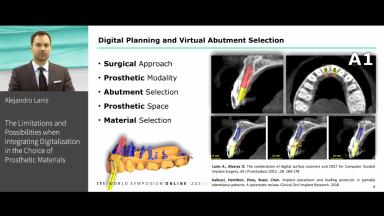

Digital technology is revolutionizing the medical field. CAD CAM dentistry is now being applied as a standard of care giving the clinician a wide broad of options when placing and restoring dental implants. From surgical planning to restorations manufacture, the amount of data managed under the digital workflow is contributing to optimize treatment time, costs and results.

In the following lecture we will discuss in detail how to choose the appropriate material in different clinical situations. We will observe the limitations and possibilities of different materials and procedures and analyze scientific evidence to obtain predictable guidelines for successful and long-lasting treatment outcomes.

- To identify the indications of CAD CAM materials in the restoration of dental implants.

- To understand the digital workflow for the restoration of dental implants.

- To become familiar with clinical pathway of digital implant placement and cad cam restoration